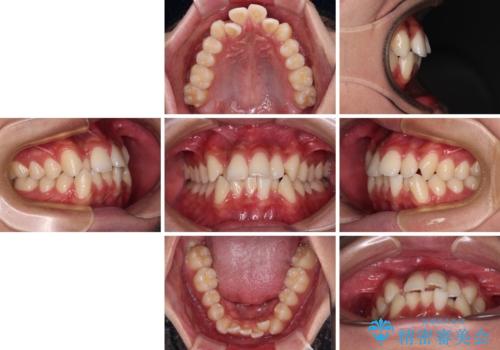

- 八重歯と口元の閉じにくさを気にして来院された患者様です。

非抜歯矯正で歯列を整えると、治療後に口元が今よりも突出する可能性が高かったため、上下左右の第一小臼歯4本を抜歯し、ワイヤー装置にて矯正治療を行うこととしました。

患者様の望んでいた通りの歯列や口元に仕上げることができました。